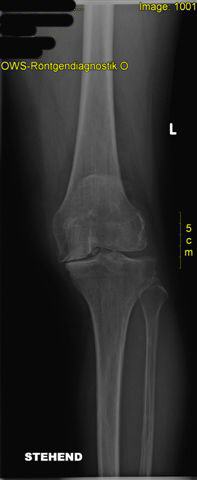

postoperativer Zustand mit liegender zementierter Knieprothese und gerade gestellter Beinachse